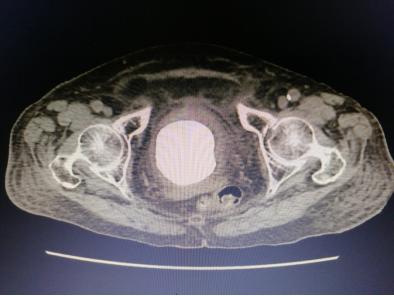

入院后,经过专业的全面系统检查后,我院泌尿外科专家组针对李老太病情召开了联合会诊。李老太的结石犹如鹅蛋般大小,而且已引起一系列严重并发症,不及时取出结石将造成更严重后果,对于一个91岁高龄而且身体情况欠佳的老太太来说采取哪种手术方案都有弊有利。

暨南大附属一院泌尿外科卓育敏主任分析:“为她选择治疗方案的时候必须慎重,因患者年龄大,多项器官功能都有明显衰退而且膀胱已无多少操作空间,开放手术虽很快可以完成,但一个7-8公分的伤口对她来说就是一个很大的创伤,很容易发生脂肪液化,尿漏等并发症,这对老人都可能造成不可预测的影响。而采用经尿道手术近乎无创,但这种结石最坚硬,又那么大,手术时间肯定很长,医生累且不说,一台高功率碎石机连续多小时的工作可能都扛不住会死机,要准备2台机器轮番上阵,要避免器械对老太膀胱黏膜损伤。”

此外,患者腰椎处压缩骨折,骨质疏松严重,心肺功能差,对麻醉的选择也是一种考验。专家团队仔细分析后,决定给老太太行细针硬外麻经尿道肾镜钬激光膀胱碎石取石术。一根纤细的纤维肾镜轻松地进入了老太太的膀胱,可以见到膀胱内的巨大结石与膀胱壁几乎紧密接触,找到缝隙后一点一点逐步击碎结石,将结石粉末化处理,并用吸引器将膀胱内碎石多次吸出,反复多次,最终将结石干净彻底清楚。手术圆满成功,手术进行了近4个小时,患者术中情况生命体征都很稳定。